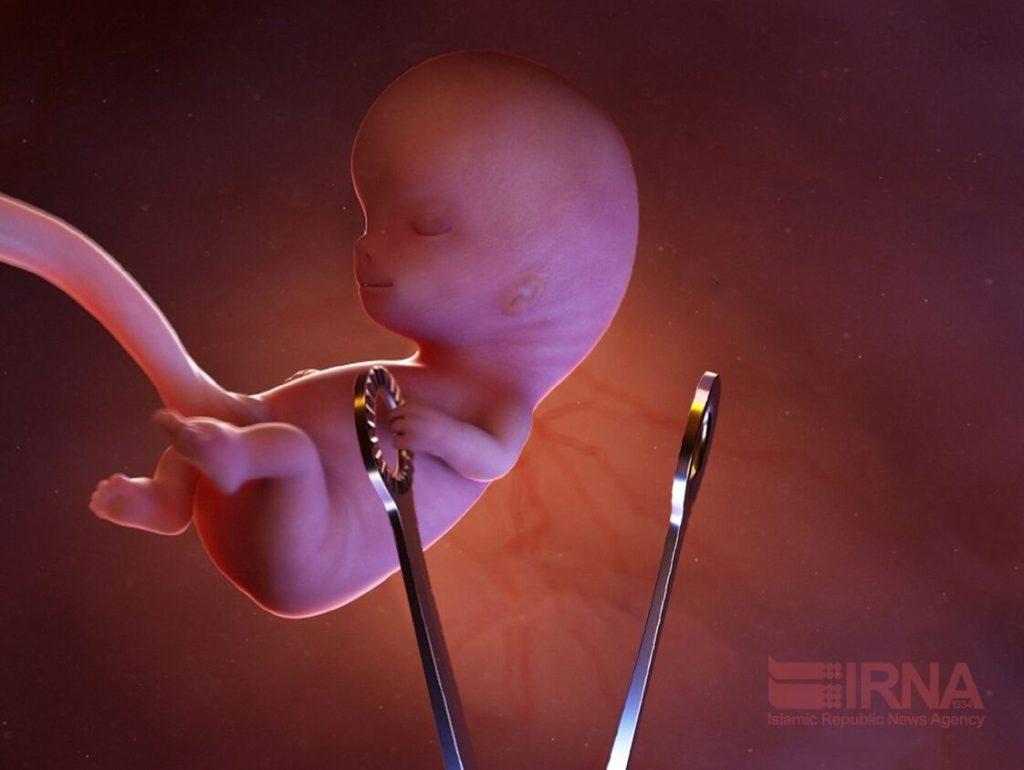

تهران – ایرنا – وزارت بهداشت، درمان و آموزش پزشکی، چهار عاملی که سقط جنین را در کشورمان به مرز بحران رسانده است؛ اعلام کرد.